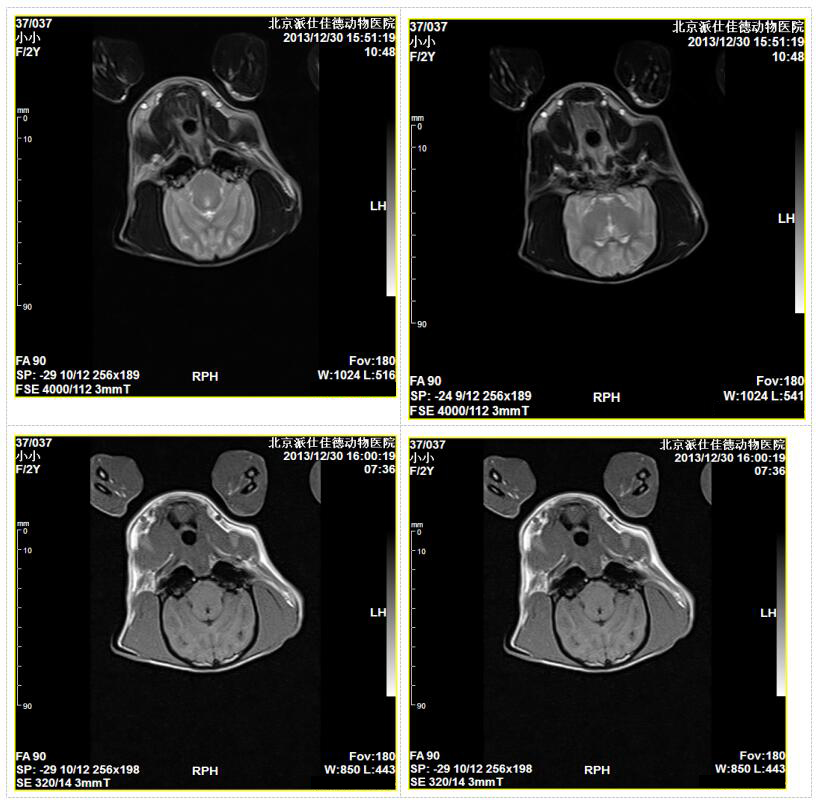

该款动物磁共振成像设备为我公司在从事多年人医磁共振设备研发 的基础上,为提高国内外动物医学影像的诊断水平,花费大量的人力、物力研发而成。

具有人医磁共振设备的所有优势,更具有占地面积小,开放度大、设备运行成本低,故障率低,操作简便智能优点。可以大大满足各类动物医院在无创伤情况下的动物医学影像检查和诊断。